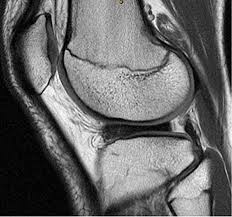

Meniscal tear can be well appreciated on an mri. In humans they are present in the knee, wrist, acromioclavicular, sternoclavicular, and temporomandibular joints; In other animals they may be present in other joints.

During knee flexion, the menisci are pulled dorsally by the femoral condyles.

Circle of villis angiogram anatomy mri. The posterior horn is always larger than the anterior horn. Meniscus rupture can occur with a sharp movement in the lateral direction, or in a direction that goes beyond the. Magnetic resonance (mr) imaging of the knee and ankle is playing an increasingly important role in the detection, diagnosis and prognosis of these injuries and their associated complications.